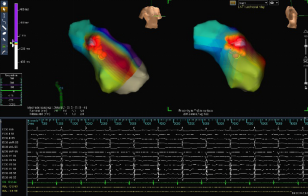

心内电生理检查是一种微创介入检查技术,通过静脉插入一根至几根特制的直径2-3毫米左右的电极导管,沿静脉送入心脏内,记录并标测心内电活动、应用各种特定的电脉冲刺激,确定心律失常的机制和引起心律失常的异常部位,藉以诊断心律失常,拟定最佳治疗方案,为射频消融术提供帮助。

射频消融术是通过微创介入手段治疗心律失常的方法,是根治快速型心律失常的首选方法。经外周血管将直径2-3mm的消融导管送至心腔内,根据心内电生理检查结果定位消融部位,释放射频电流,导致局部心肌发生凝固性坏死,从而阻断快速心律失常异常传导束和起源点,达到根治心律失常的目的。经导管向心腔内导入的射频电流损伤范围在1-3 mm,安全有效。

我院心血管中心拥有先进的DSA室、三维标测系统,已成功开展心内电生理检查、射频消融术、心脏起搏器植入术等治疗技术,治疗效果肯定,我们愿为广大患者竭诚服务。